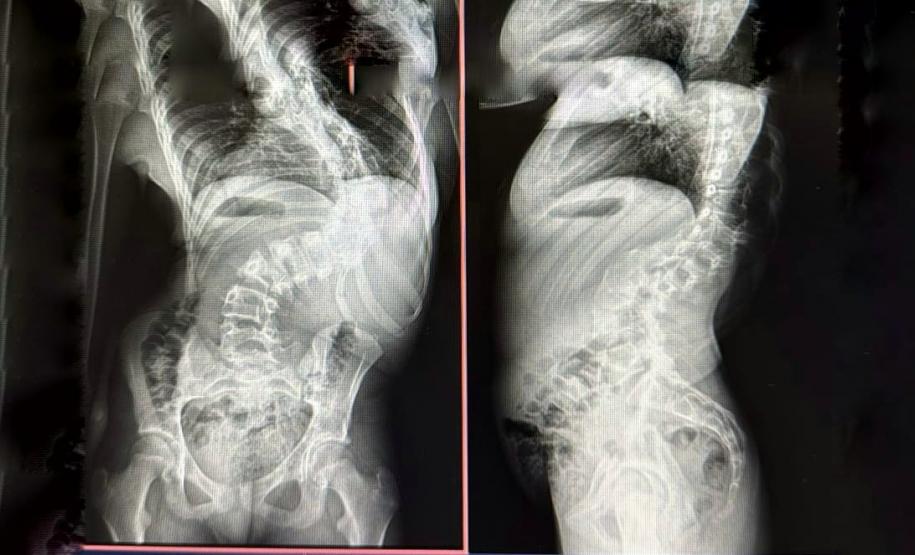

Quando criança, Lays Cristina Souza Felix, atualmente com 13 anos, residente do município de Campo Mourão, enfrentou um grande desafio ao ser diagnosticada com escoliose infantil, uma deformidade na coluna que pode causar dores intensas e, em casos mais graves, comprometer funções respiratórias e cardíacas. Para corrigir o problema, ela passou mais de um mês internada no Hospital de Reabilitação, unidade do Complexo Hospitalar do Trabalhador (CHT), onde foi submetida a um tratamento com tração por halo craniano para preparar sua coluna para a cirurgia.

Na última terça-feira (25), a paciente passou pelo procedimento corretivo e agora segue em recuperação, com previsão de alta ainda nesta semana. A menina faz parte dos pacientes atendidos pelo Serviço de Deformidades Pediátricas da Coluna Vertebral do CHT.

A escoliose pode ter diferentes causas, sendo classificada em idiopática (sem causa definida), sindrômica (associada a síndromes genéticas que afetam o desenvolvimento ósseo), neuromuscular (decorrente de doenças como paralisia cerebral e atrofia muscular espinhal) e congênita (presente desde o nascimento). Em todos os casos, o diagnóstico precoce e o acompanhamento especializado são fundamentais para determinar a melhor abordagem terapêutica, que pode incluir o uso de coletes ortopédicos, gesso, fisioterapia e, quando necessário, cirurgia.